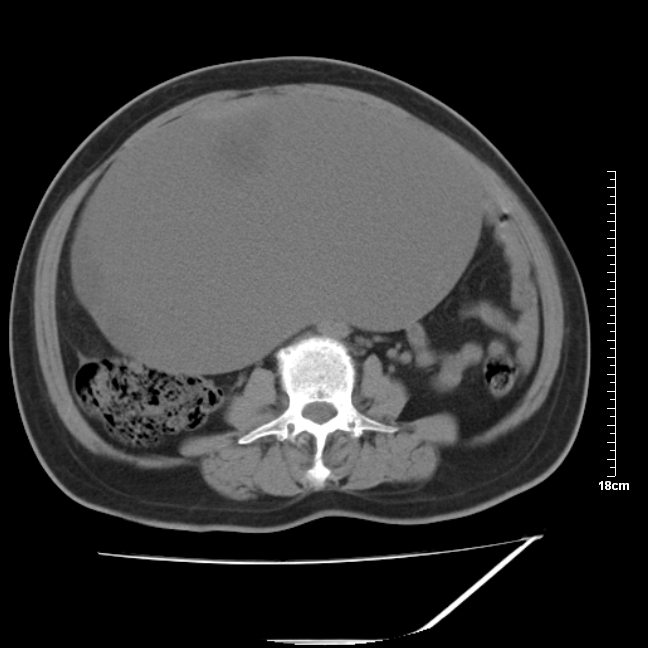

以下是引用jinning在2007-5-17 11:18:00的发言:[br]考虑右侧卵巢囊腺瘤合并少量出血可能性大